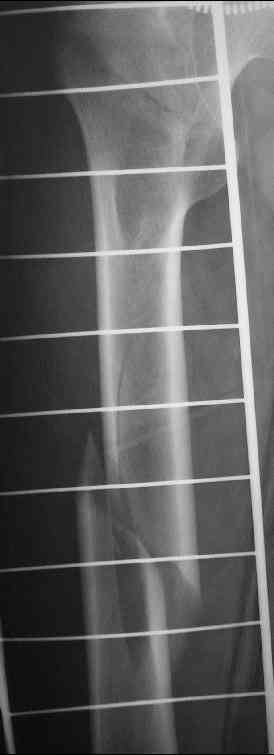

Уважаемые коллеги,пару дней назад к нам поступил пациент 54 лет с таким вот переломом правого бедра. Сейчас на скелетном вытяжении. Хотелось бы услышать мнения по поводу природы округлого просветления в подвербельной области (аневризмальная киста?)и тактики лечения.

Dear all, a few days ago a 54 y.o. patient was admitted to our hospital with this fracture of the right femur. Now he is on a skeletal traction. I'd appreciate your opinion as to: 1.the nature of a lucent lesion (?) in subtrochanteric area - is it ABC? 2.treatment options.Thanks, Peter Romchuk, Central City Hospital, Rivne, Ukraine.С уважением, Петр Ромчук, ЦГБ г.Ривне, Украина

По-моему, самое значимое то, что этот очаг не похож на первичную опухоль, особенно злокачественную. Вопрос, следами какого опухолеподобного заболевания этот очаг является, носит больше академический интерес. Для уточнения характера этого очага желательно сделать еще снимки в других проекциях, если доступно - КТ. Можно сделать биопсию из небольшого разреза.

Идеально было бы сделать остеосинтез длинным гамма гвоздем или другими похожими фиксаторами. Каковы собственные планы?

We need to make a diagnosis of the lesion and also treat the fracture. If I had not noticed the luscent lesion, I would have straightaway treated him with a long PFNail.

Having noticed that lesion will not change my decision. Only that when my centering awl goes into the shaft thro the trochanter, I will be careful to save the material it comes out with and send it for histopathology. I would also do a

skeletal survey before the surgery to see any other lesion.

It is not obligatory pathological fracture. May be the radiolucensy in subtrochanteric area is the part of the fracture. I think that CT can be good answer for this question.

If you have not PFN - the DHS + DFN may resolve the problem with fixation of these fractures.

Do not forget to take biopsy at time of operation.